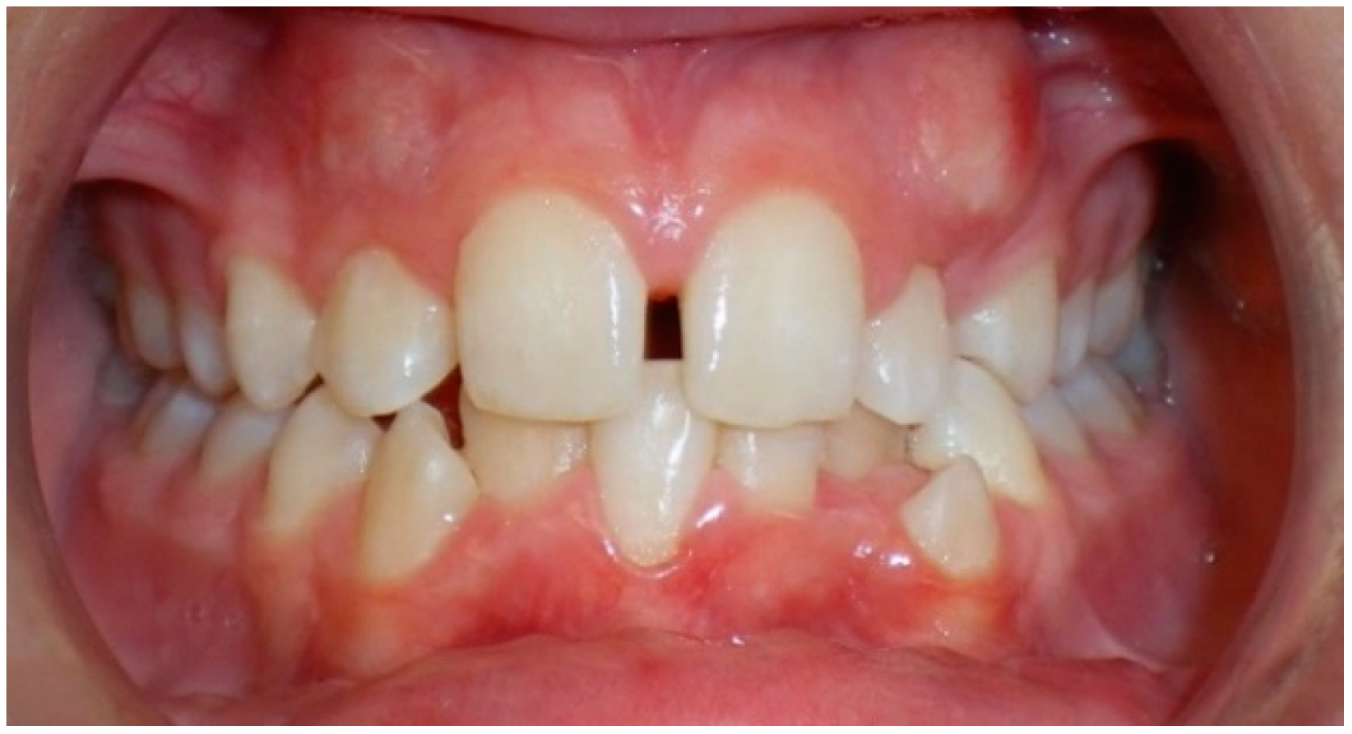

- Evaluation of buccal and lingual cortical plates: Figure 5, Figure 6 and Figure 7 show a case in which the mandibular lateral incisors are positioned lingual to the central incisors. Both mandibular lateral incisors are adjacent to each other. Figure 5 shows and intraoral occlusal photos with retained deciduous mandibular lateral incisors. There was no way to evaluate the buccal and lingual cortical plates through conventional 2D panoramic, periapical or occlusal radiographs. Therefore, CBCT was acquired and collimated to the area of teeth in order to assess the relationship of the four mandibular incisors to the labial and lingual cortical plates as well as to the adjacent teeth. As Figure 6 and Figure 7 display, CBCT shows that all permanent mandibular incisors are sound. It is important to note that thin buccal and lingual cortical plates may not be seen via CBCT—this does not denote that they are not present. In other words, CBCT images may not show a clinically present thin buccal and lingual cortical plates. In this case, the diagnostic information obtained from CBCT is far more significant than the information obtained from any other radiographic imaging technique.